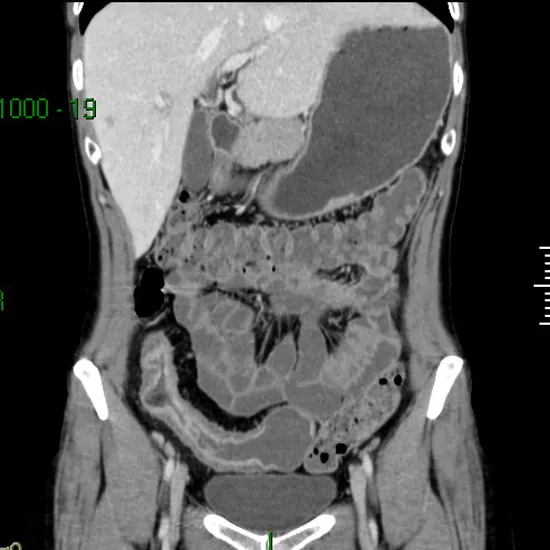

CT Enterography (Computerized Tomography Enterography) is an imaging test. It uses contrast media and provides detailed images of tissues and the structure of the small intestine. It is recommended to detect disorders of the small intestine such as inflammation, tumours, bowel obstructions and bleeding. It is helpful to check the efficacy of an intestinal disorder treatment. It is also performed if a patient is having symptoms of Crohn's disease such as diarrhoea, abdominal cramps, bleeding in stool etc.

CT Enterography test scan shows issues related to the small intestine like inflammation, infection, injury, cancer, obstruction etc. The price of the CT Enterography test scan typically ranges from INR 7,000 to INR 14,000 in Delhi NCR.